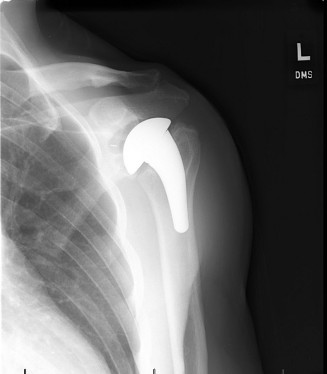

Diagnostic shoulder arthroscopy 85 Shoulder arthroplasty 108 Arthroscopic procedures 90 Viva questions 112 Op…